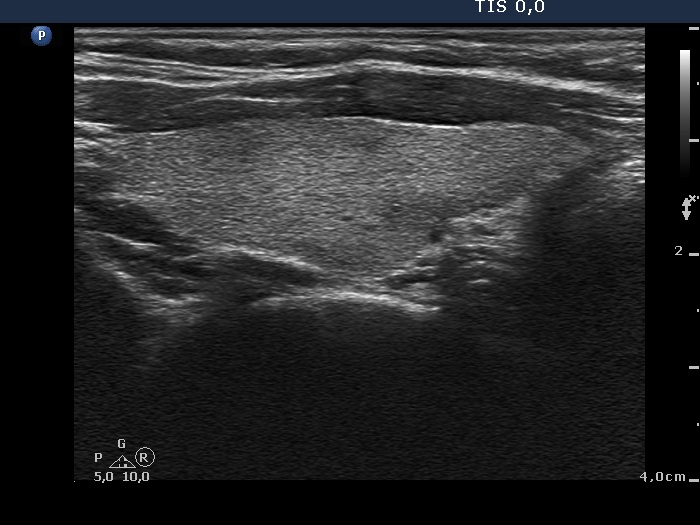

Initial examination (first row of images):

Clinical presentation: A 39-year-old woman was referred for evaluation of neck complaints lasting for more than a month. The patient had fever, neck pain. She has got two courses of antibiotics and non-steroid anti inflammatory drugs which had no effect.

Palpation: The right lobe was painful and hard while the left lobe was tender.

Laboratory examination: TSH 0.01 mIU/L, FT4 29.1 pM/L, FT3 7.45 pM/L, CRP 31.2 mg/L.

Ultrasonography: The thyroid presented with hypoechoic areas which had blurred borders. The echogenicity index was approximately 65% in the right and 20% in the left lobe. The thyroid was almost completely avascular.

Diagnosis: subacute, granulomatous de Quervain's thyroiditis.

Suggestion. Steroid therapy was suggested.